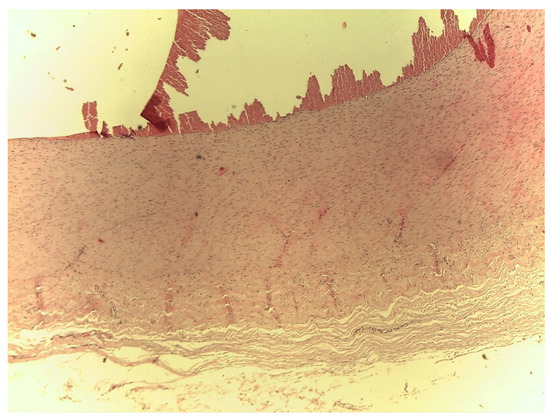

Histopathology

The histological test showed no differences between the three different neck cutting locations. In general, fragments of a clot could be seen lying on the vascular endothelium, arranged in an irregular fashion (Figure 2) and evident distension of the elastic and muscular fibres, characterized in some areas by irregularity and interruption (Figure 3). Moreover, swelling at the distal end of the artery was associated with erythrocytes and fibrin trapped within the connective tissue sheath surrounding the artery. On the other hand, there were no signs of blood infiltration within the artery wall, suggesting that this formation was not a true aneurysm.

Figure 3.

Bovine carotid artery with false aneurysm. Mallory's trichrome (40×).